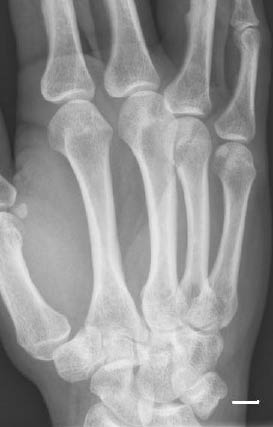

Figure 4: Triquetral Fracture

Patients with injury to the triquetrum report pain with wrist flexion and extension, along with swelling of the dorsum of the wrist.20 Patients may have localization of the pain over the dorsum of the wrist distal to the ulnar styloid. Triquetral fractures are best visualized on oblique and lateral wrist radiographs. (See Figure 4.) Patients with dorsal ridge chip fractures should be placed in a short-arm, well-padded ulnar gutter splint. Patients with triquetral body fractures that have greater than 1 mm of displacement are associated with perilunate and or lunate dislocations. Injuries of this nature should have immediate referral because they may require operative intervention.12